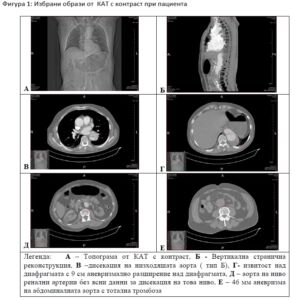

Фигура 1: Избрани образи от  КАТ с контраст при пациента

A Б

В Г

Д Е

Легенда:   А – Топограма от КАТ с контраст, Б – Вертикална странична реконструкция, В –дисекация на низходящата аорта ( тип Б), Г– извитост над диафрагмата с 9 см аневризмално разширение над диафрагмата, Д – аорта на ниво ренални артерии без ясни данни за дисекация на това ниво, Е – 46 мм аневризма на абдоминалната аорта с тотална тромбоза

хирург. При посочения статус се прие ОАН на долни крайници и се извърши повторна  КАТ  с контраст, включваща съдовете от дъгата на аортата до тазовите артерии. Находките са показани на Фигура 1. Комбинацията от демонстративния и драматичен клиничен синдром на ОАН в съчетание с показаната находка на КАТ изследването ни даде основание за приемане на диагноза тромбоза на ААА на фона на латентно протичаща дисекация на гръдната аорта тип Б и формиращо се  аневризмално разширение на аортата над диафрагмата. При консултация с кардиохирург бе отхвърлена каквато и да е техническа възможност за оперативно лечение по отношение на сегментите с дисекация и аневризмално разширение над диафрагмата.

За съжаление не бе извършена абдукция. Базирано на клиниката при постъпването, КАТ изследването и клиниката при екзитуса, наше убеждение е, че причина за смъртта е прогресиране и руптура с масивна хеморагия  на аневризмалната находка над диафрагмата с размер от 9 см при постъпването, Фигура 1, Г. При преглед на ред обзори с големи серии от пациенти се очертава факта, че именно не решаването на  проксималният проблем при дисекация на аортата е свързано с лошата прогноза след успешно оперативно лечение на съдовите усложнения на коремната аорта и дисталните съдове (8,26). Днес с развитието на TEVAR съществуват ред нови възможности за повлияване именно при някои пациенти с дисекация на аортата тип Б и даващи шанс за по-добър изход. За съжаление при нашият пациент нямаше такава възможност.